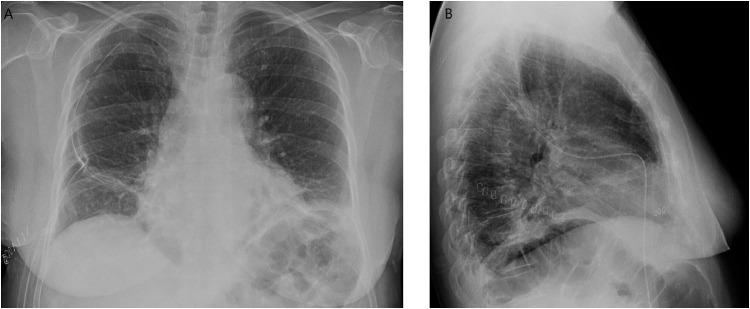

Lipoma is the most frequent benign soft-tissue tumor. It originates from fat cells. According to position, it is distinguished in superficial, typically subcutaneous lipoma, or deep, such as intramuscular lipoma. This latter form is infrequently and may resemble well-differentiated liposarcoma. For this reason, early radiological detection and characterization are necessary to obtain a wide complete resection and histopathologic evaluation to differentiate benign from malign lesions. We report an extremely rare case of an intrathoracic intramuscular lipoma of the chest wall detect and characterize with chest X-ray and computed tomography examinations, resected with thoracoscopic intervention and confirmed with histopathologic analysis.

脂肪瘤是最常见的良性软组织肿瘤。它起源于脂肪细胞。根据位置,可分为浅表性脂肪瘤,通常为皮下脂肪瘤,或深部脂肪瘤,如肌内脂肪瘤。后一种类型较为少见,可能类似于高分化脂肪肉瘤。因此,早期进行放射学检测和特征分析对于实现广泛的完整切除以及进行组织病理学评估以区分良性和恶性病变是必要的。我们报告了一例极其罕见的胸壁胸内肌内脂肪瘤病例,通过胸部X线和计算机断层扫描检查进行检测和特征分析,经胸腔镜干预切除,并经组织病理学分析确诊。